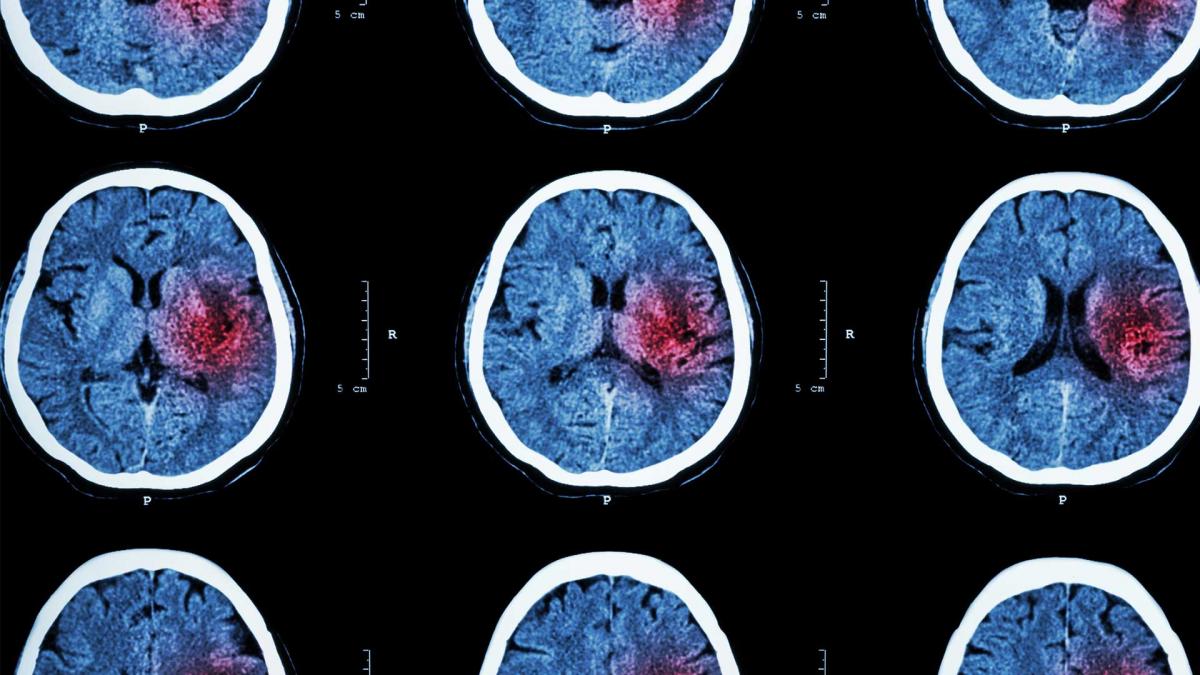

MRI scan

What happens when there is a bleeding in the brain or a brain artery is blocked? Meet “Stroke”! Stroke is a leading cause of death and disability in Australia. Join in a live conversation with Dr Sonu Bhaskar on how to recognise stroke symptoms, latest breakthroughs in acute stroke treatment, and the importance of rapid access to time-critical therapies.